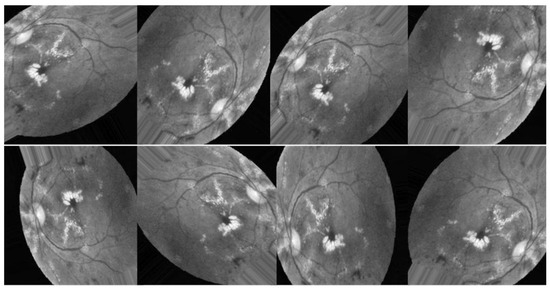

All previous edits to images in the training set are applied to generate new samples for the network. While the total number of images is the same in all scenarios, Figure 8, Figure 9 and Figure 10 illustrate the purpose of data augmentation, which is to increase the quantity of data by providing slightly altered copies of the existing data or newly synthesized data derived from the existing data using the same parameters in all three scenarios. Here are the three scenarios that were used to train DenseNet-121:

In the first scenario, shown in Figure 8, researchers augment the improved images using CLAHE and ESRGAN.

Figure 8. Examples of augmenting the same image with different methods (CLAHE + ESRGAN).